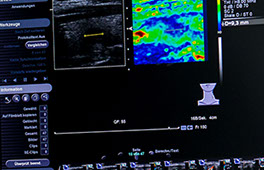

Bei der Elastografie der Leber wird vor allem auf diffuse Veränderungen des Lebergewebes geachtet: Je härter, fester Lebergewebe erscheint, desto mehr Bindegewebe ist in der Leber entstanden, desto eher entwickelt sich eine Leberzirrhose, also der Verlust funktionsfähiger Leberzellen zugunsten funktionsunfähiger Bindegewebszellen.

Je früher dieser Prozess erkannt wird, desto eher können Gegenmaßnahmen ergriffen werden. Ein häufig anzutreffendes Beispiel: Beim sonografischen Verdacht für das Gewebebild einer Fettleber (die eben auch ohne die Wirkung von Alkohol entstehen kann) bestehen auch bei nur gering oder gar nicht erhöhten Laborparametern ("Leberwerten") bereits Entzündungsvorgänge ("Hepatitis"), die einen solchen Umbau des Lebergewebes zur Folge haben.

Mit früher Kenntnis von diesen Umbauvorgängen können durch entsprechende Maßnahmen (z.B. Diätempfehlungen, evtl. medikamentöse Therapie, Planung von Verlaufsbeobachtungen etc.) die Spätfolgen entweder vermieden oder zumindest deutlich verzögert werden. Dies gilt insbesondere für Patienten mit einer chronischen Virus-Hepatitis oder einer der selteneren Leberentzündungen infolge einer Störung des Immunsystems.